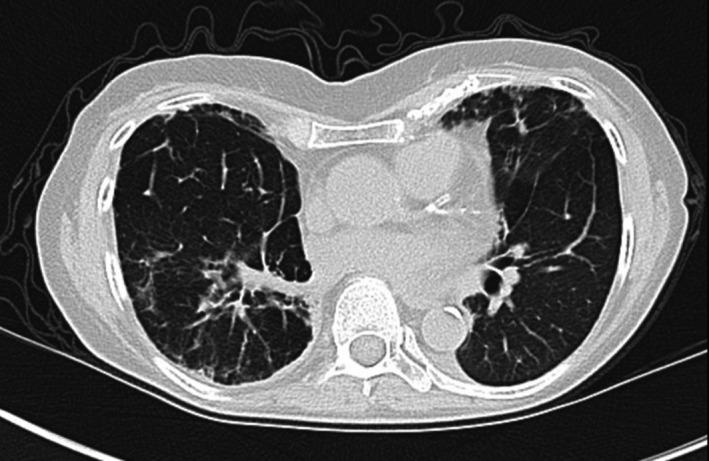

Bosutinib-associated interstitial lung disease and pleural effusion: A case report and literature review.

Bosutinib is a tyrosine kinase inhibitor approved for the management of chronic myeloid leukemia (CML). Interstitial lung disease and pleural effusion are pulmonary side effects of TKIs rarely associated with bosutinib treatment.